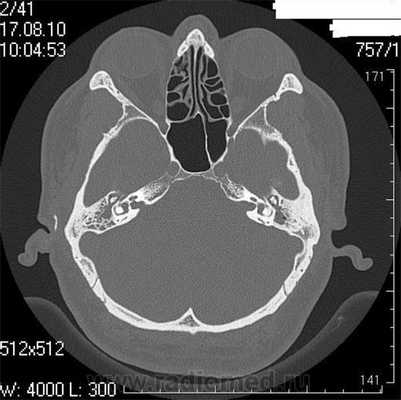

Во время КТ получают послойные снимки височной кости и окружающих тканей в трех плоскостях. Толщина среза составляет всего несколько миллиметров, что позволяет врачу-рентгенологу рассмотреть не только все анатомические образования, но и минимальные патологические изменения.

На полученных снимках хорошо видны следующие структуры:

пирамида височной кости;

ячейки и антрум сосцевидного отростка;

улитка, преддверие, передний и задний полукружный каналы;

слуховые косточки среднего уха;

стенки наружного слухового прохода;

Снимок (томограмма) височных костей в осевой проекции